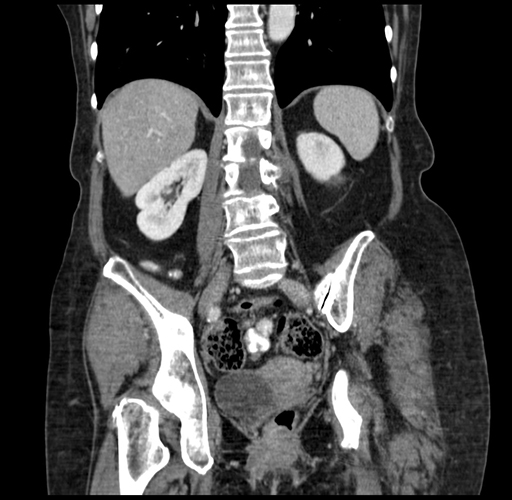

Pre-Chemo: Coronal Venous

Coronal Venous